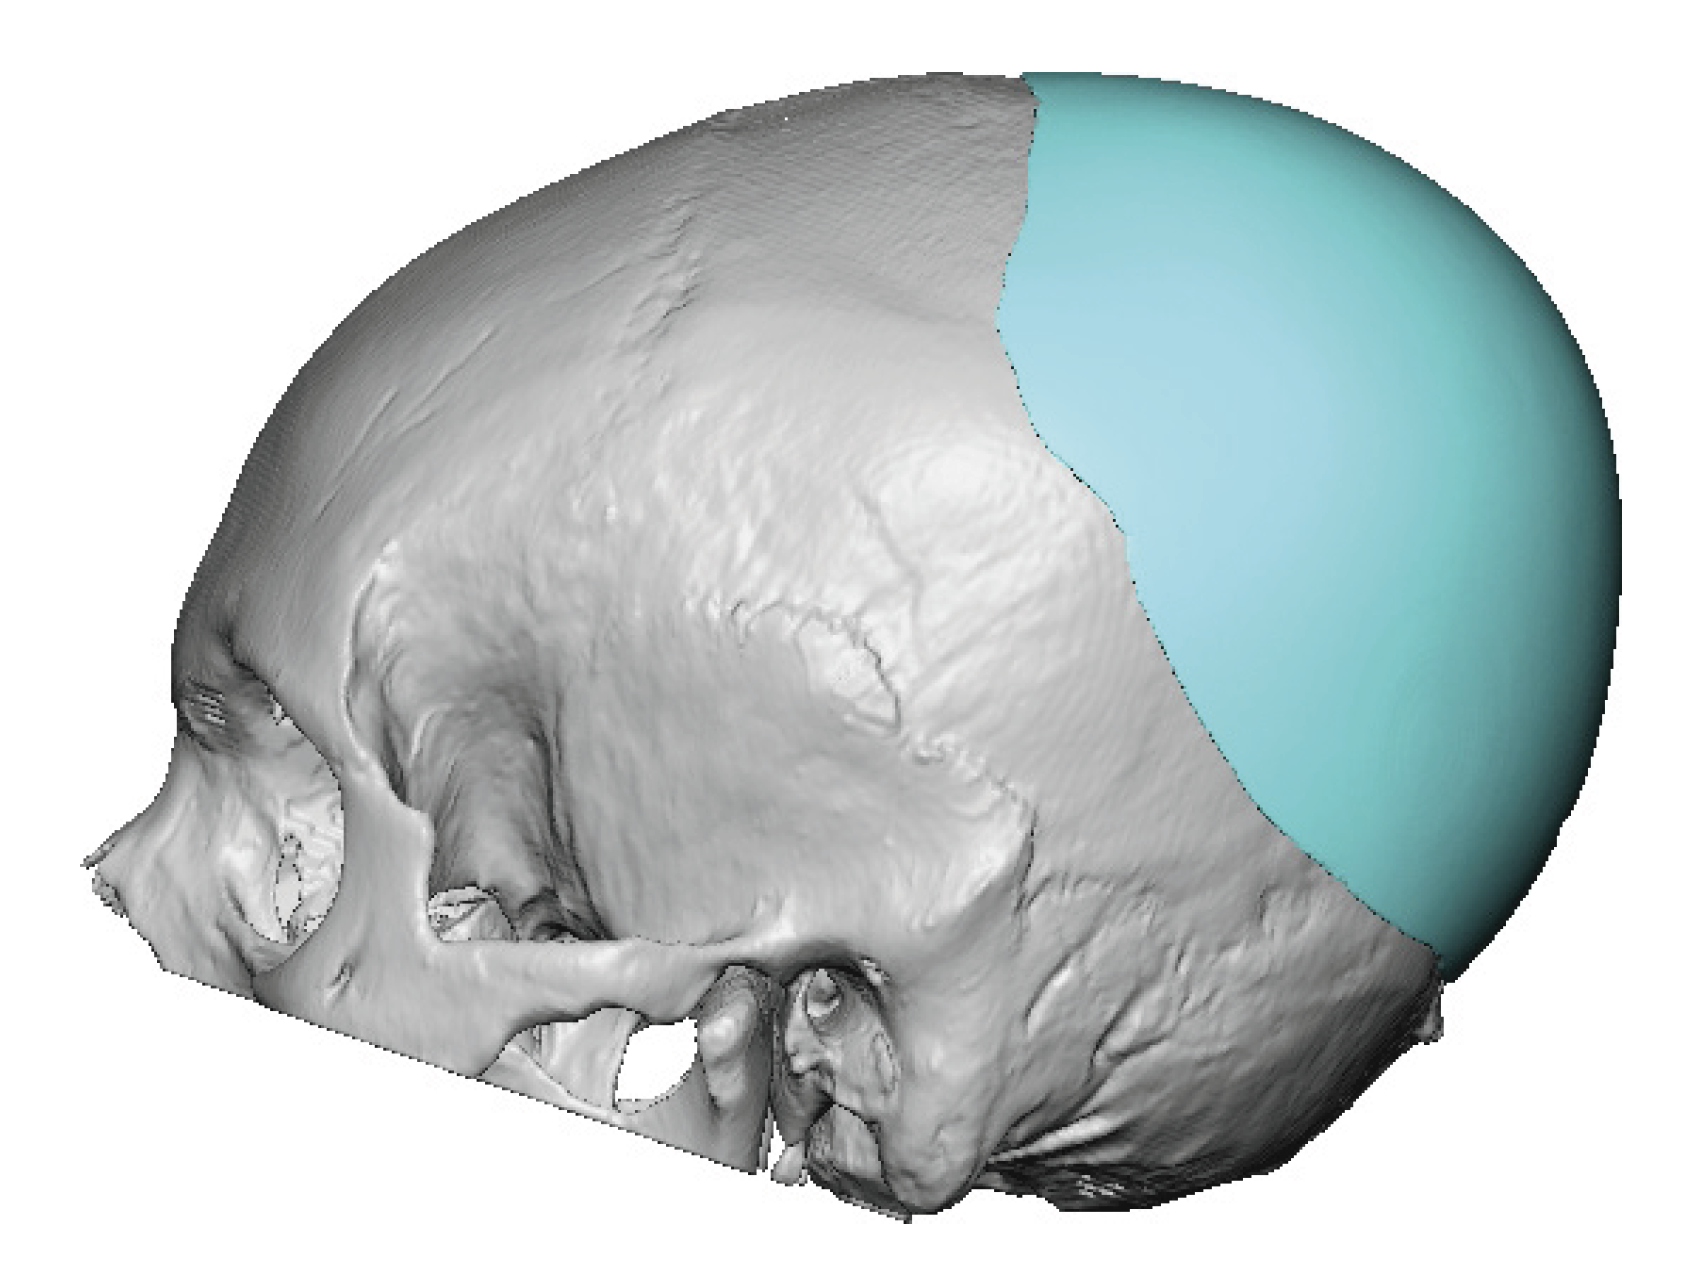

Severe narrowing skull deformity from prior sagittal craniosynostosis repair as an adult.

Complete replacement of entire skull by a custom implant with temporal fat injections.

Severe narrowing skull deformity from prior sagittal craniosynostosis repair as an adult.

Complete replacement of entire skull by a custom implant with temporal fat injections.